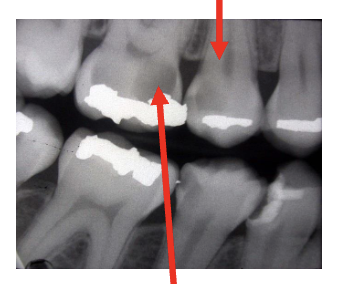

Is this a candidate for a pulp cap?

A

Upper arrow: may be candidate

Lower arrow: certainly not a candidate for indirect cap - probably already a direct exposure